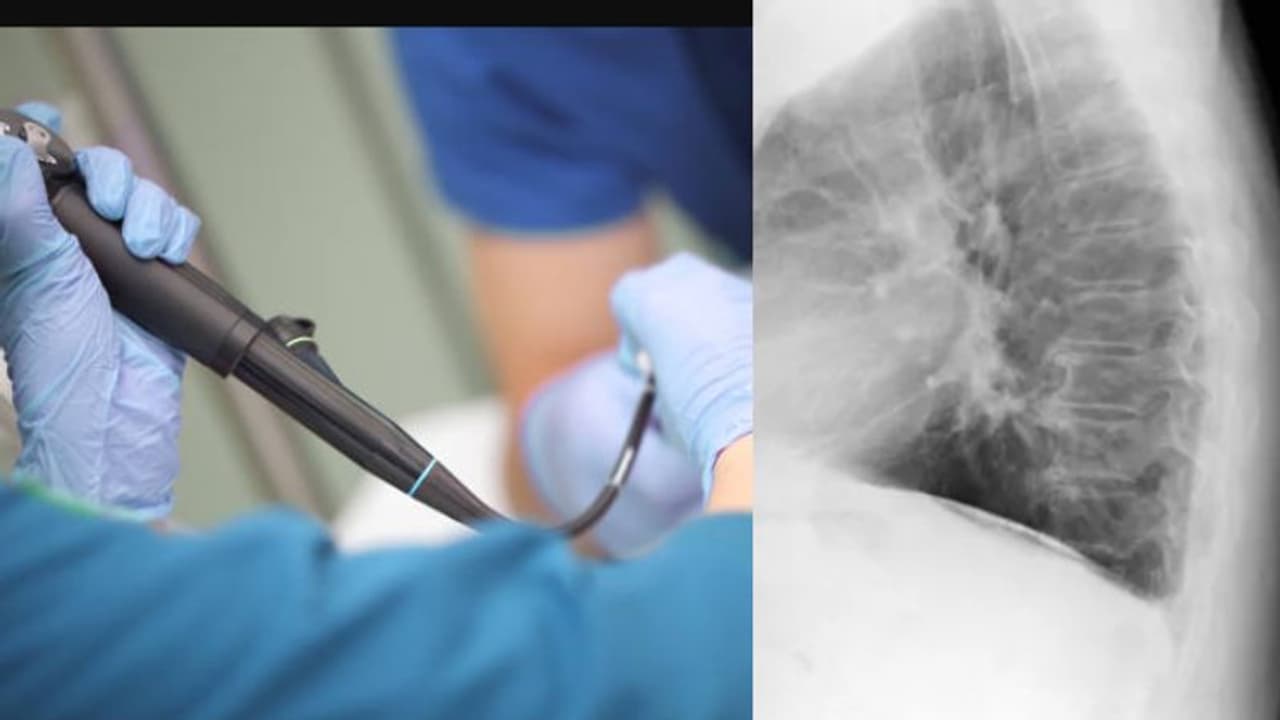

മലപ്പുറം: ബാലികയുടെ ശ്വസനനാളത്തിൽ ഒരു മാസം മുമ്പ് കുടുങ്ങിയ നിലക്കടല ബ്രാങ്കോസ്ക്കോപ്പിയിലൂടെ പുറത്തെടുത്തു. പെരിന്തൽമണ്ണ മൗലാന ആശുപത്രിയിലാണ് സംഭവം. താഴേക്കോട് സ്വദേശിയായ രണ്ടു വയസ്സുകാരികാരിയുടെ ശ്വസനനാളത്തിലാണ് നിലക്കടല കുടുങ്ങിക്കിടന്നിരുന്നത്.

അപ്പോഴാണ് ശ്വസനനാളത്തിൽ എന്തോ കുടുങ്ങിക്കിടക്കുന്നത് ശ്രദ്ധയിൽപ്പെട്ടത്. തുടർന്ന് കൺസൾട്ടറ്റ് ഇന്റർവെൻഷണൽ പൾമ നോളജിസ്റ്റ് ഡോ. നിമിഷ ബ്രോങ്കോസ്കോപ്പിയിലൂടെ നിലക്കടലയുടെ കഷ്ണം പുറത്തെടുക്കുകയായിരുന്നു. അനസ്തേഷ്യവിഭാഗം മേധാവി ഡോ. പി ശശിധരൻ, ശിശുരോഗ വിഭാഗത്തിലെ ഡോ. അനീഷ എന്നിവരും പങ്കാളികളായി.